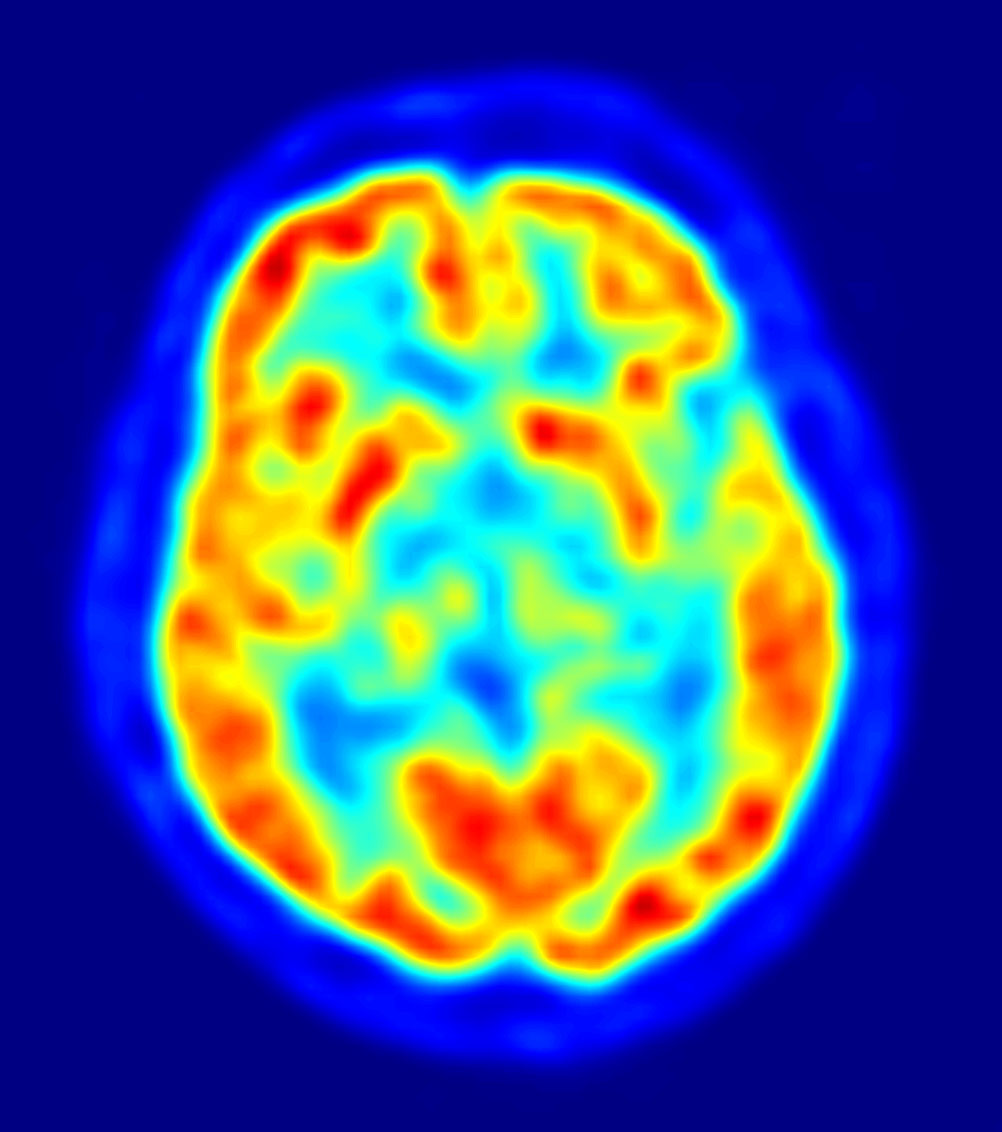

PET image of the human brain showing energy consumption